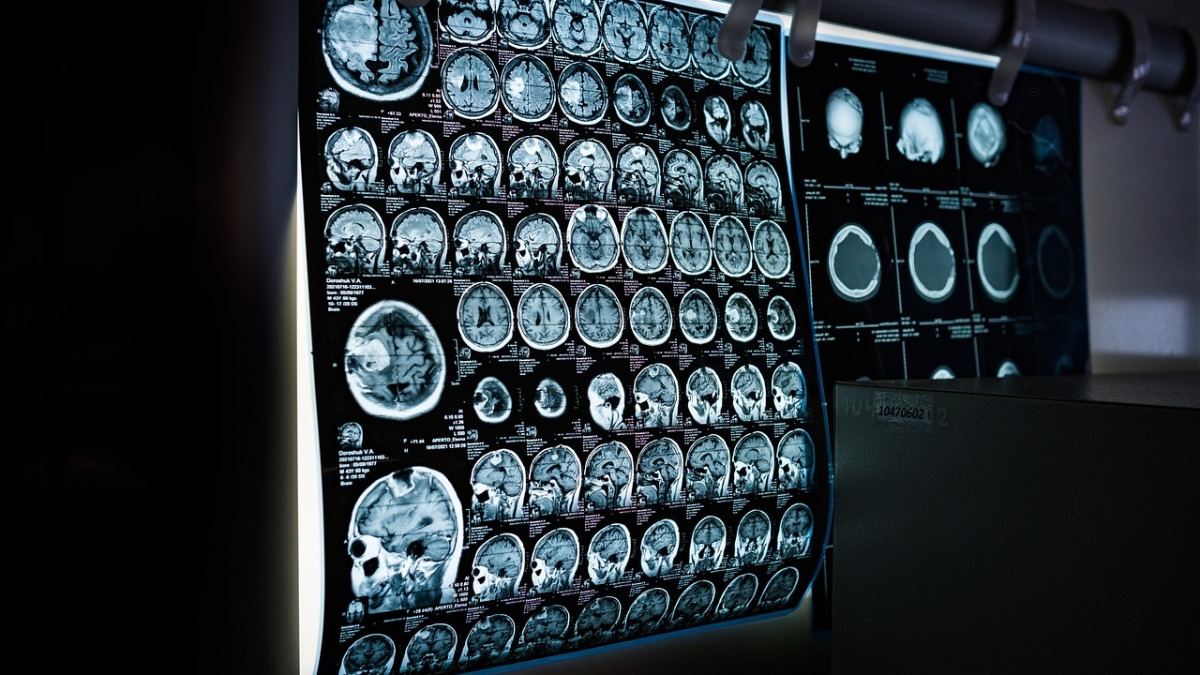

Stručnjaci došli do tajne zašto mozgovi nekih ljudi ne stare

Neki ljudi zadržavaju oštar um i u svojim osamdesetim i kasnije, rušeći ideju da je kognitivno opadanje neizbježno kako starimo. Jedna 25-godišnja studija o ovim zavidnim pojedincima sada otkriva šta je posebno u vezi s njihovom neurologijom.

Vajntraub i njezine kolege otkrili su da su mozgovi određenih ljudi neobično otporni na nagomilavanje proteinskih naslaga i zapleta tipičnih za Alchajmerovu bolest. Ovi pojedinci takođe imaju veću koncentraciju jednog specifičnog tipa neurona u ključnom dijelu mozga, kao i manje znakove upalnih procesa u bijeloj masi mozga u poređenju s tipičnom starijom populacijom.

Vajntraub i njezin tim pratili su 290 osoba starih 80 i više godina od 2000. godine, kako bi usporedili one koji su se pokazali kao „superstarci“ s onima koji stare tipično. Zahvaljujući velikodušnim donacijama 79 mozgova „superstaraca“, istraživači su identificirali neke ključne biološke razlike.

Ćelije koje prenose informacije ka hipokampusu, poznate kao entorinalni neuroni, bile su veće kod superagera, što je, prema mišljenju istraživača, možda doprinijelo njihovoj otpornosti ili izdržljivosti.

Štoviše, kod tipično starećih osoba primijećeno je stanje stanjivanja vanjskog sloja mozga, dok se kod „superstaraca“ to nije dešavalo. Ovaj dio mozga kontroliše svjesne misli, pamćenje i jezik.

„Superstarci“ su takođe imali više fon Ekonomovih neurona i deblji prednji cingulatorni korteks, gdje se ti neuroni nalaze, čak i u poređenju sa znatno mlađim ljudima. Taj dio mozga učestvuje u reguliranju pažnje, emocija i donošenja odluka.

Prethodne studije već su pokazale da ovaj dio mozga kod superagera ne smanjuje zapreminu kao što se očekivalo. Vajntraub i njezin tim sumnjaju da su „superstarci“ rođeni s većom gustoćom fon Ekonomovih neurona.

Zajedno, ove razlike izgleda da održavaju njihov mozak stabilnim tokom vremena.